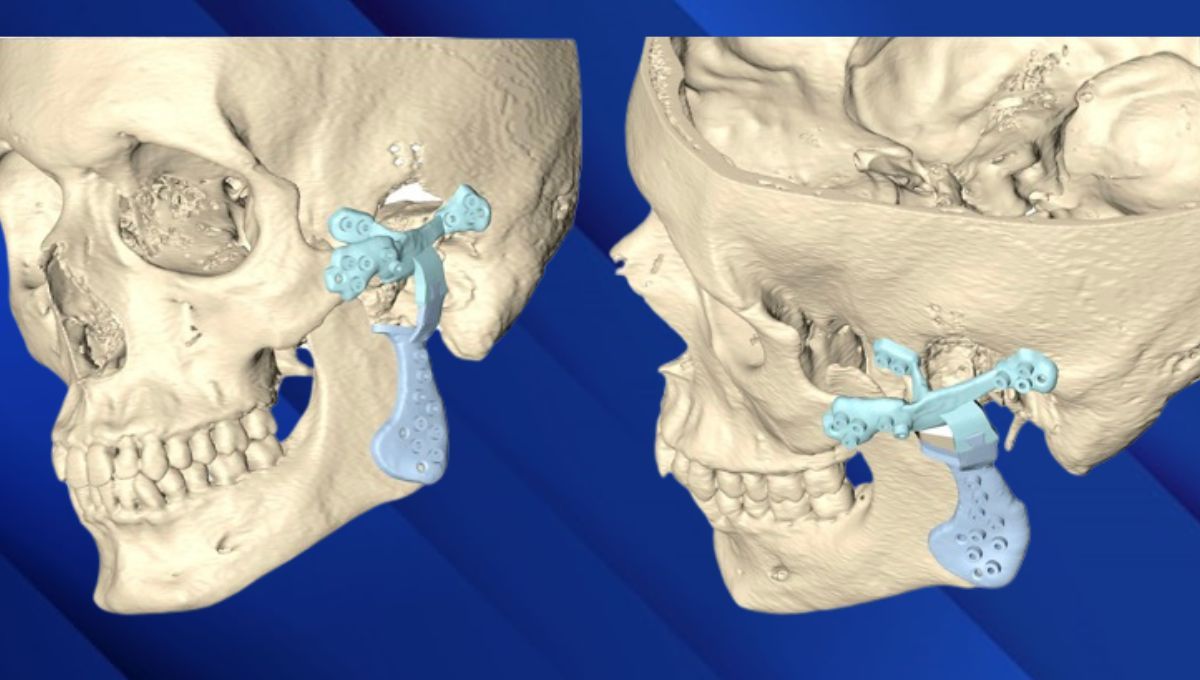

Tal y como recuerda el Dr. Néstor Montesdeoca, todo el mundo tiene un cóndilo y una fosa distinta, especialmente después de la extirpación de un tumor, ya que la anatomía cambia completamente tanto en esos casos de tumores como de anquilosis, artrosis, reabsorciones, etcétera. “La anatomía que entendemos como tal ha desaparecido, lo que obliga a diseñar una prótesis en 3D a medida del defecto. El proceso se hace juntamente con ingenieros biomédicos para asegurarnos de que cumple los requerimientos mecánicos, anatómicos y funcionales específicos de cada paciente. Cuando verificamos que el diseño funciona, lo aprobamos, mandamos a fabricar y operamos al paciente”.

El diseño de la prótesis afecta a oclusión, debe fabricarse de manera que los dientes encajen completamente, “es decir, no sirve de nada que abras y cierres la boca si no consigues que los dientes encajen al cien por cien”. Por tanto, son necesarios registros y escáneres tanto de la cara como de la mordida para que, en la simulación de dónde hay que colocar la prótesis, los dientes contacten adecuadamente con la boca cerrada y la prótesis esté en el lugar deseado, haciendo correctamente el juego de apertura y cierre. Para ello utilizamos guías quirúrgicas de posicionamiento diseñadas específicamente para cada prótesis”.